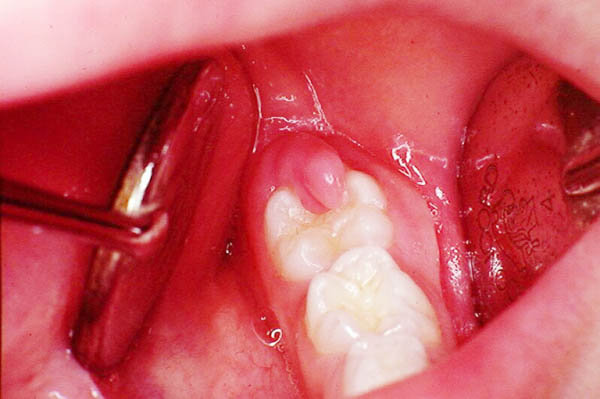

Viêm nướu quanh thân răng (pericoronitis)

Đây là nguyên nhân phổ biến nhất gây đau răng khôn, đặc biệt khi răng đang trong quá trình mọc:

- Cơ chế hình thành: Khi răng khôn mọc một phần, phần nướu còn phủ lên răng tạo thành một “nắp nướu” (operculum). Thức ăn và vi khuẩn tích tụ dưới nắp nướu này, không thể vệ sinh được.

- Quá trình viêm: Vi khuẩn sinh sôi nảy nở gây viêm nướu, tạo ra các chất trung gian gây viêm kích thích dây thần kinh, dẫn đến đau nhức.

- Mức độ nghiêm trọng: Viêm nướu quanh thân răng có thể từ nhẹ (chỉ đỏ và đau nhẹ) đến nặng (sưng lớn, mủ, khó nuốt, khó mở miệng).

- Mọc một phần: Chỉ một phần của răng khôn nhô lên khỏi nướu, phần còn lại bị “kẹt” dưới xương hoặc nướu, tạo điều kiện cho vi khuẩn xâm nhập.

- Cắt nắp nướu (operculectomy): Trong một số trường hợp, bác sĩ có thể cắt bỏ phần nắp nướu đang phủ một phần răng khôn để giảm viêm và ngăn tái phát